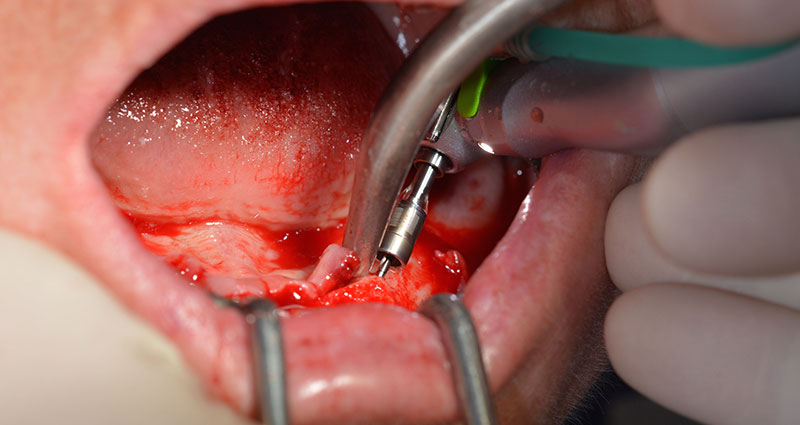

El siguiente ajuste programado es la propia inserción de los implantes. En nuestra clínica, solemos insertar los implantes con una fuerza de 32 Ncm de manera estándar (figs. 12 y 13).

El requisito imprescindible para el tratamiento inmediato es una alta estabilidad primaria. Para satisfacer dicho requisito, en este caso, se prescindió del corte de rosca. La unidad de accionamiento Implantmed de W&H empleada aquí, posee un modo propio para ello que también puede seleccionarse directamente y resulta imprescindible para muchas indicaciones. Los últimos giros para la inserción del implante superaron el valor de 32 Ncm, por lo que se realizaron manualmente. En tales casos, se recomienda utilizar la función autocortante de los implantes y girar el implante varias veces hacia delante y hacia atrás de forma que el implante se aproxime gradualmente hasta su posición definitiva sin ejercer una presión excesiva sobre el hueso (fig. 14).